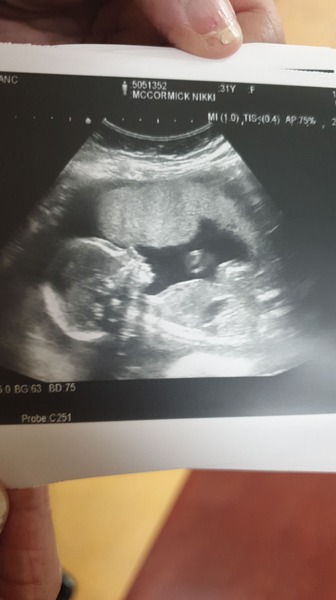

nikdan123 · 11/11/2019 12:48

We had our 20 week scan this morning, Its a BOY!! Absolutely over the moon and still in shock as I was adamant it was a girl.

April 2020 Babies - Thread 2!

nikdan123 · 11/11/2019 12:59

I havent felt any movements yet either, I am 19 + 1 but saw him moving plenty this morning.

Oh wow beautiful scan! Congratulations on your little boy! We’re convinced we’re having a girl based on no science I must add!! but my partner doesn’t want to find out officially at the scan darn it! I’m hoping the angle of the scan will allow guessing!!